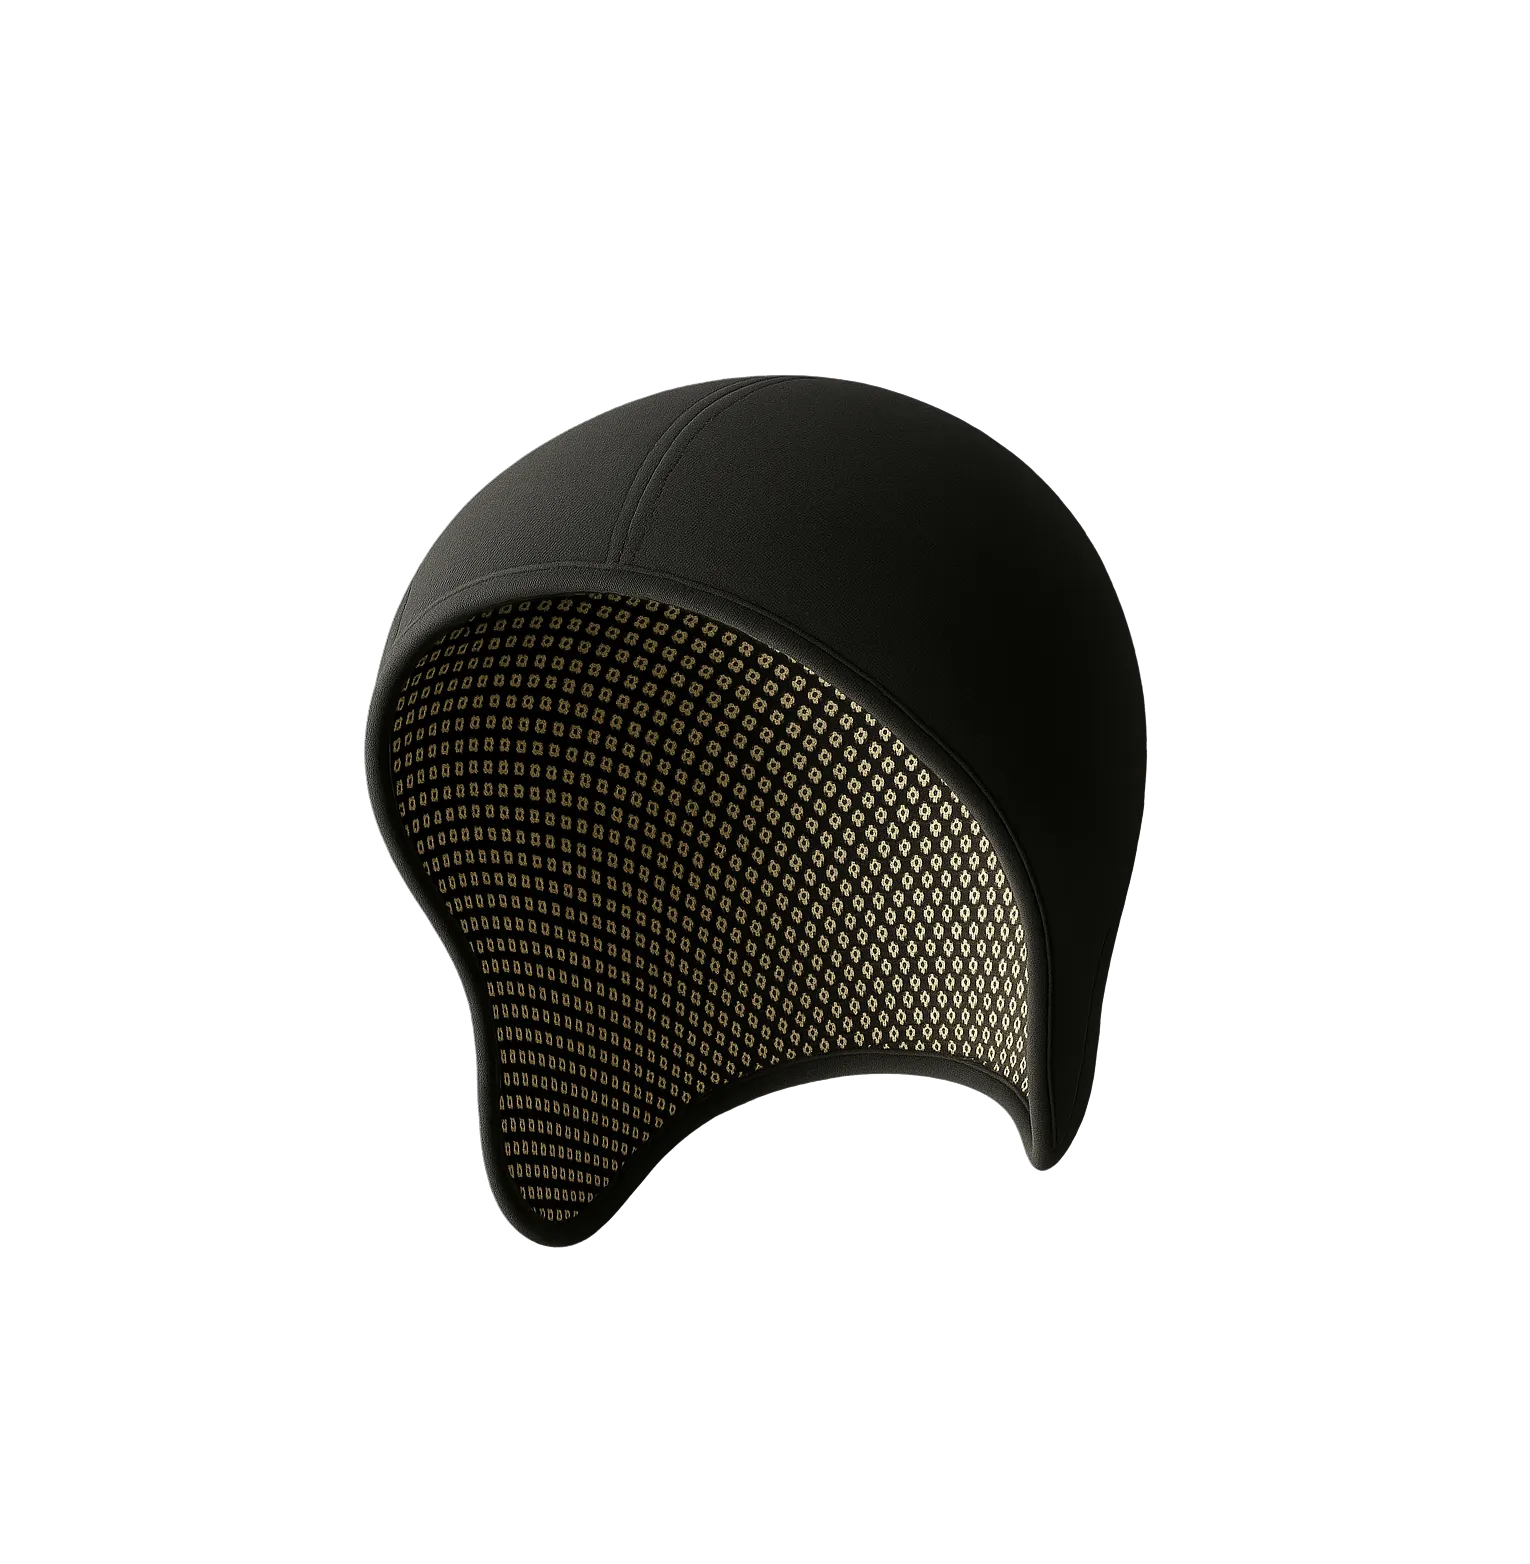

High-density signal acquisition

A 256-channel, fabric-based EEG cap that patients can wear like a beanie, delivering hospital-grade EEG instantly, without a technician or glue.

A Smart, High-Density EEG Cap for Home or Clinic

Neuralace replaces the technician, the adhesive, the bulky hardware, and the delays with a lightweight, high-density EEG cap (<200g) that patients can apply themselves.

Key Features

- 64–256 channel high-density EEG

- Wearable fabric cap (beanie/baseball style)

- Self-applied by patient in minutes

- No adhesive, no glue, no abrasion

- Wireless streaming to phone or laptop

- 24-hour battery + 30-minute rapid recharge

- Real-time EEG access for clinicians

- Automated electrode localization using a photo

- Dense sensor architecture enabling spatial accuracy